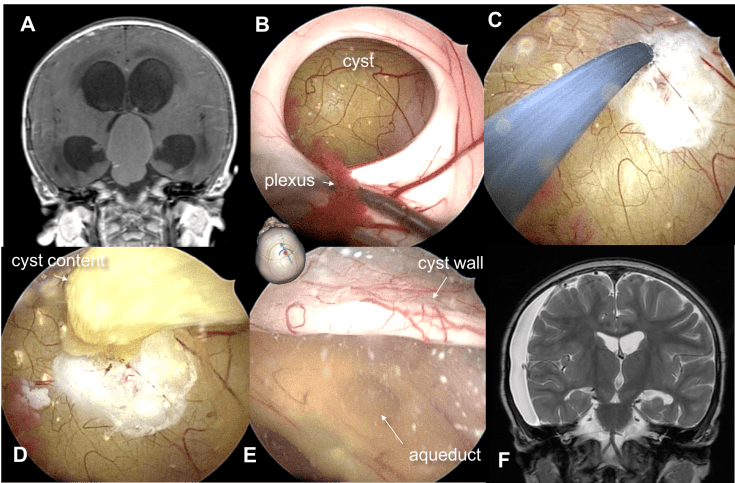

l’ouverture de la lame terminale permet d’accéder au contenu du V3 et de le faire descendre sous le chiasma (cf. ci-contre).

le traitement du kyste

il est souvent nécessaire en urgence à la phase initiale. il peut également devenir nécessaire en cas de progression kystique tardive. la radiothérapie est peu ou pas efficace sur les kystes. on peut réaliser :

- une fenestration endoscopique cf. ci-dessous

-

catheter intra-kystique pour curie-thérapie par Rhénium une ponction stéréotaxique avec mise en place d’un cathéter pour ponction-vidange, ou traitement intrakystique

- curie-thérapie par béta-emetteur (Rhénium)

le traitement du kyste est essentiellement un traitement d’urgence ou d’appoint qui n’est en règle pas suffisant chez l’enfant.